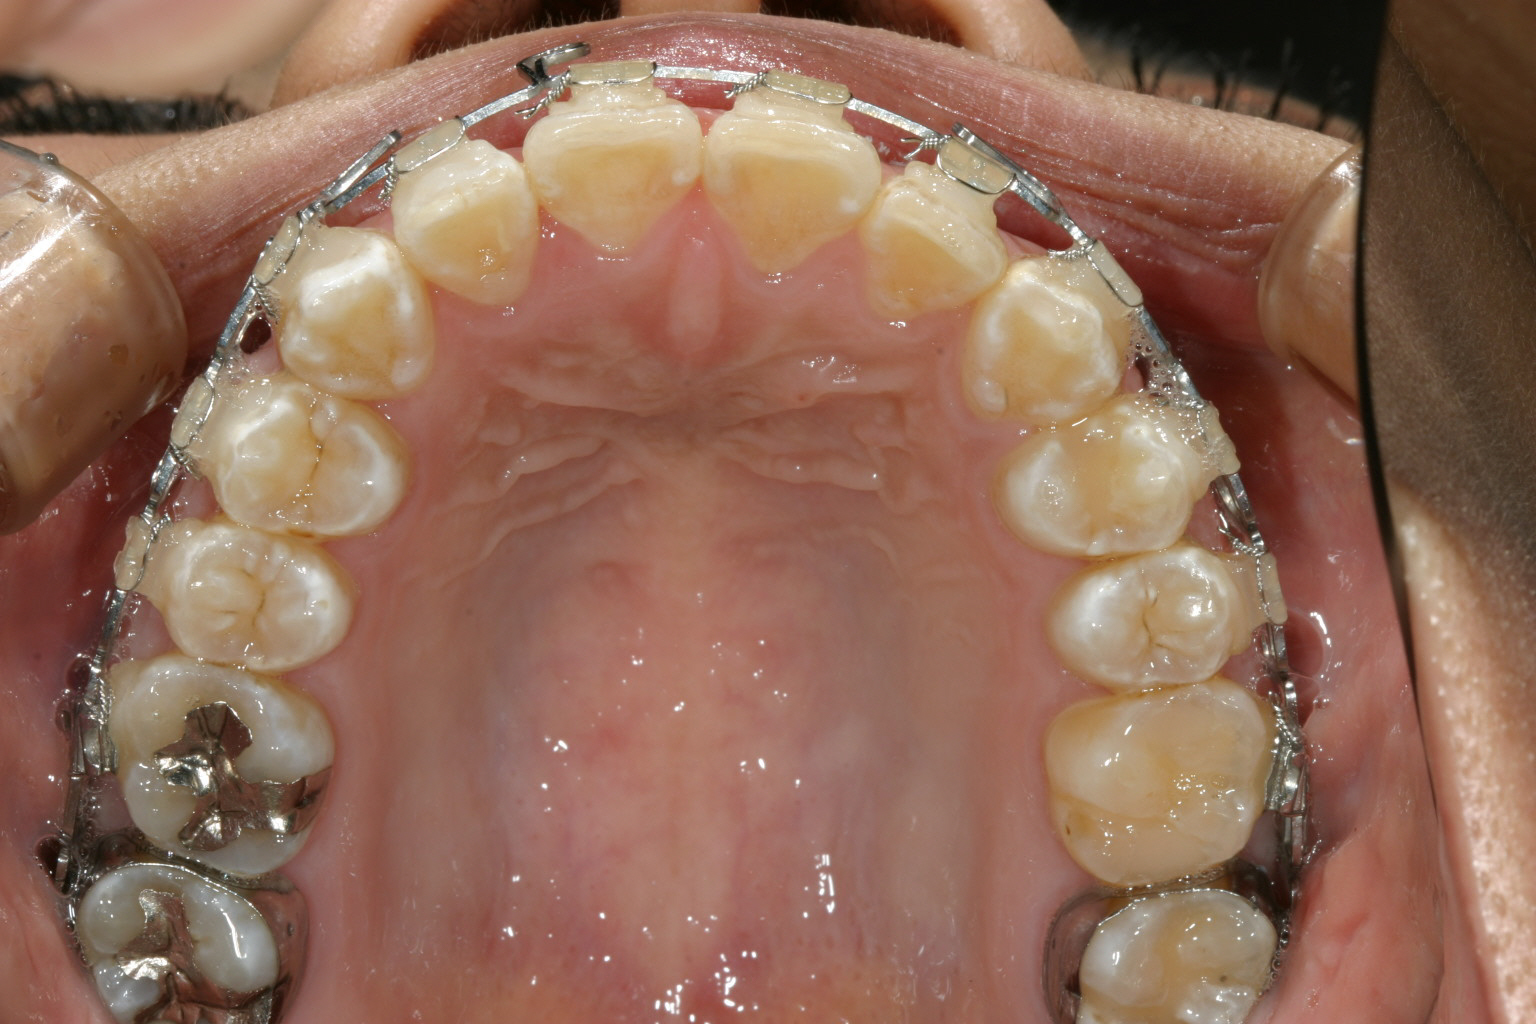

右上の犬歯が飛び出しているのが気になります。

マルチループワイヤー使用で3ヵ月です。 もう殆ど犬歯の飛び出し改善してます。

下顎もマルチループワイヤーしています。